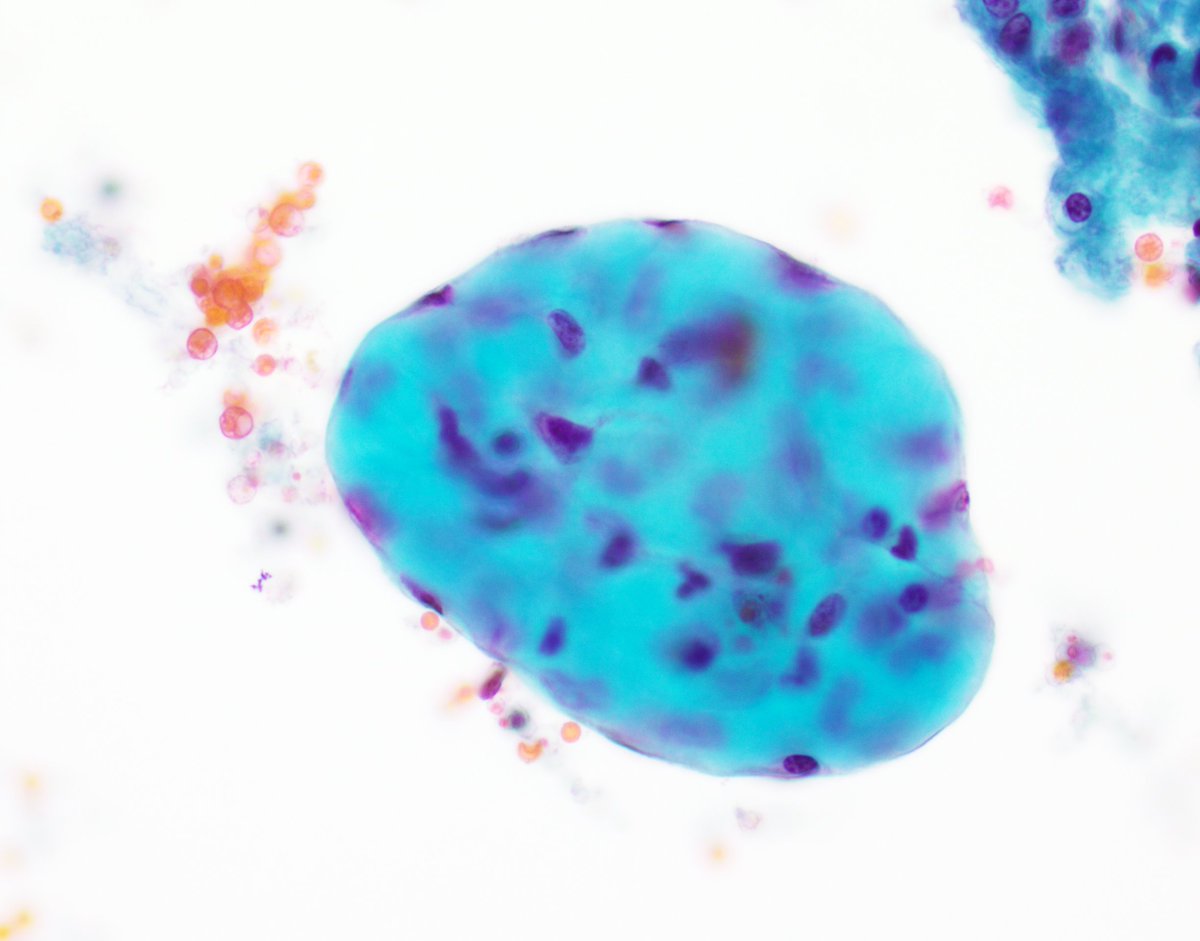

For trainees->nice exp of collagen ball in a pelvic wash sample. Not to be confused with adenoca (which may be seen as 3D structures w community borders). Collagen balls r seen in up to half of pelvic washings & r spherical masses of collagen lined by mesothelial cells #CytoPath

VandaTorousMD's tweet image. For trainees->nice exp of collagen ball in a pelvic wash sample. Not to be confused with adenoca (which may be seen as 3D structures w community borders). Collagen balls r seen in up to half of pelvic washings & r spherical masses of collagen lined by mesothelial cells

#CytoPath